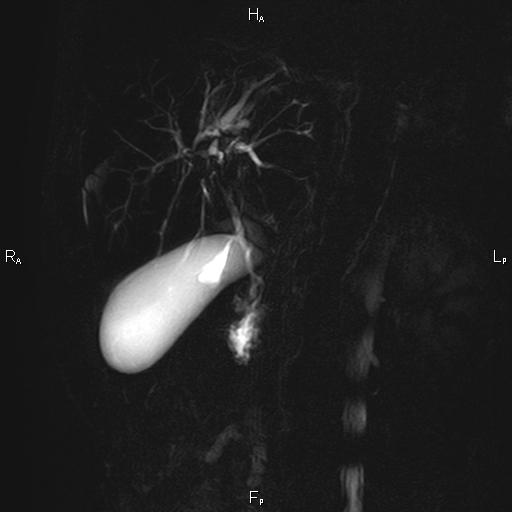

ΚΛΙΝΙΚΑ ΣΤΟΙΧΕΙΑ – ΙΣΤΟΡΙΚΟ

Ανώδυνος ίκτερος και παθολογικά ηπατικά ένζυμα. Ιστορικό πιθανής σκληρυντικής χολαγγειίτιδας

ΑΠΕΙΚΟΝΙΣΤΙΚΟΣ ΕΛΕΓΧΟΣ

Μαγνητική τομογραφία.

Οι αρχικές εξετάσεις εκλογής, όσον αφορά τον απεικονιστικό κυρίως έλεγχο, σε ασθενή προσερχόμενο στο Νοσοκομείο με αποφρακτικό ίκτερο, είναι το υπερηχογράφημα και η αξονική τομογραφία. Οι εξετάσεις αυτές έχουν αποδειχθεί ικανές να προσδώσουν έμμεσα και άμεσα στοιχεία για τη διάγνωση του χολαγγειοκαρκινώματος, όμως κυρίαρχη εξέταση για την διάγνωση του χολαγγειοκαρκινώματος είναι η μαγνητική τομογραφία (MRI, MRCP, MRA).